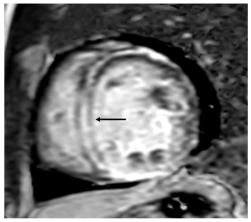

| Imaging Modality | Imaging Illustrations | Description |

|---|---|---|

| Cardiac MRI | ![]() | Short-axis view reveal interventricular mid-myocardial LGE (black arrow). |